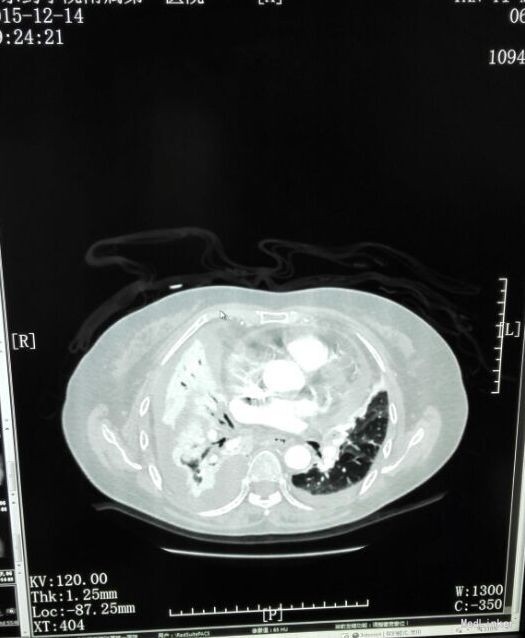

患者入院后予“美洛西林舒巴坦”抗感染,当天晚上出现明显气促,伴右后下背痛,无明显发热,当时复查胸片示: 1、双下肺炎症、双侧胸腔积液,同2015.12.13前片比较,考虑右侧胸腔积液明显增多,部分包裹,建议CT进一步检查。血气分析未见明显异常,2015-12-14 复查急诊血常规:白细胞计数 24.290(10E9/L)↑,淋巴细胞计数 0.750(10E9/L)↓,中性粒细胞比例 0.930↑,血红蛋白浓度 104.000(g/L)↓,中性粒细胞计数 22.590(10E9/L)↑,红细胞计数 3.500(10E12/L)↓,血小板计数 466.000(10E9/L)↑,单核细胞计数 0.920(10E9/L)↑;急诊肾功(三项):尿素氮 8.450(mmol/L)↑;急诊电解质(K/Na/Cl):钠 128.700(mmol/L)↓,氯 87.100(mmol/L)↓; 2015-12-14胸部及上腹部CT平扫+增强示:1、两中下肺多发炎症,部分萎陷。建议治疗后复查。2、双侧胸腔积液(右著);心包少量积液。3、结合病史,右输尿管术改变;右侧双J管置入术后。右肾、输尿管上段扩张、积水,右肾周感染并少许积气;左肾结石。4、脂肪肝。5、胆、脾、胰未见异常。因CT提示肺部大片实变,包裹性积液(量少),考虑重症肺炎可能,于2015-12-14将抗生素升级为“亚胺培南西司他丁 1.0 q8h、万古霉素 50万U q12h、伏立康唑 0.2 q12h”三联,同时予“甲强龙”抗炎等治疗。经治疗,患者气促症状逐渐缓解,咳嗽、咳痰、右后背疼痛好转,无发热,精神、胃纳较前改善。因B超定位下胸水量少,暂未予胸穿。2015-12-17复查胸部+上腹部CT平扫示:1、双中下肺炎炎症较前吸收好转,右侧胸腔积液较前略有减少,左侧胸腔积液现已基本吸收。2、胸、腹主动脉粥样硬化;心包少量积液(大致同前)。纵膈内临界肿大淋巴结。3、右输尿管术改变;右肾、输尿管上段扩张、积水,右肾周慢性感染(原右肾周积气消失);左肾结石。4、轻度脂肪肝。少量腹水。5、胆囊内斑片状高密度影,考虑胆汁淤积。2015-12-19 复查血常规:白细胞计数 18.160(10E9/L)↑,中性粒细胞比例 0.918↑,血红蛋白浓度 105.000(g/L)↓,中性粒细胞计数 16.670(10E9/L)↑,红细胞计数 3.560(10E12/L)↓,血小板计数 396.000(10E9/L)↑,淋巴细胞比例 0.037↓,红细胞压积 0.305↓,单核细胞计数 0.780(10E9/L)↑;降钙素原 2.000(ng/ml)↑;急诊肾功(三项):肌酐 146.000(umol/L)↑,尿素氮 19.580(mmol/L)↑。2015-12-20患者精神较前明显变差,伴纳差、乏力,气促较前加重,2015-12-20再次复查血常规:白细胞计数 33.230(10E9/L)↑,中性粒细胞比例 0.967↑,红细胞计数 3.350(10E12/L)↓,中性粒细胞计数 32.130(10E9/L)↑,血红蛋白浓度 99.000(g/L)↓,单核细胞比例 0.016↓,淋巴细胞比例 0.016↓,红细胞压积 0.293↓;2015-12-20 急诊肾功(三项):肌酐 125.000(umol/L)↑,尿素氮 15.960(mmol/L)↑;降钙素原 0.836(ng/ml)↑;复查胸片示:1、同2015.12.17胸部CT比较,考虑右侧胸腔积液较前有所增多,大部分为包裹性积液,新发左侧胸腔少量积液;右肺情况显示不清,左下肺炎症。2、心影增大,结合CT考虑心包积液;主动脉粥样硬化。遂行胸腔穿刺术,抽出400ml黄白色脓性胸水,胸水常规:PH6.0,WBC54600*10E6/l,中性粒0.97,胸水生化:乳酸脱氢酶 2221.000(U/L);葡萄糖 1.180(mmol/l),总蛋白 24.000(g/l),腺苷脱氨酶 154.000(U/L),氯 106.800(mmol/L)。符合脓胸改变,予右侧胸负压腔闭式引流,同时予“庆大霉素16万u”冲洗,将抗生素降级为莫西沙星片口服,患者症状明显好转,12.24复查胸片及CT胸腔积液及肺炎均较前明显好转。